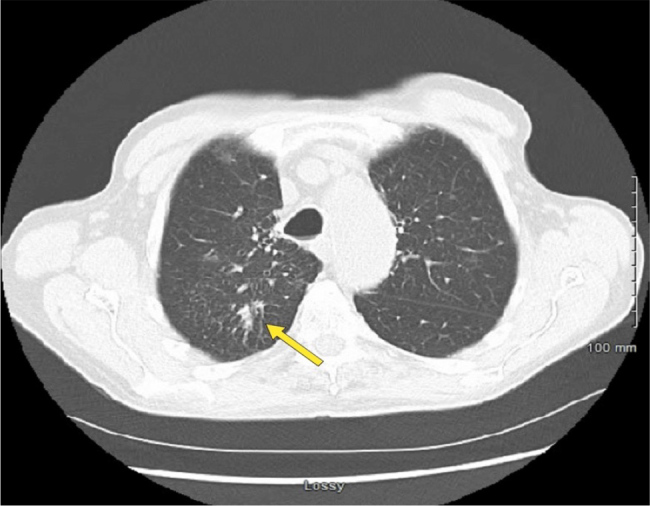

Case description: We present a case of a 78-year-old male with CLL receiving chemotherapy, who developed burning pain in the tongue and oral mucosa, accompanied by a non-productive cough. He was initially diagnosed with pneumonia, but further investigation revealed co-infection involving M. avium and S. apiospermum.

Discussion: The coexistence of M. avium and S. apiospermum underscores the complexity of infectious complications in CLL. The patient's chemotherapy was halted due to active pneumonitis observed on imaging in order to improve his leukocyte count. Antifungal therapy was not initiated due to a lack of evidence of invasive fungal infection. Antimycobacterial therapy for M. avium complex was initiated.